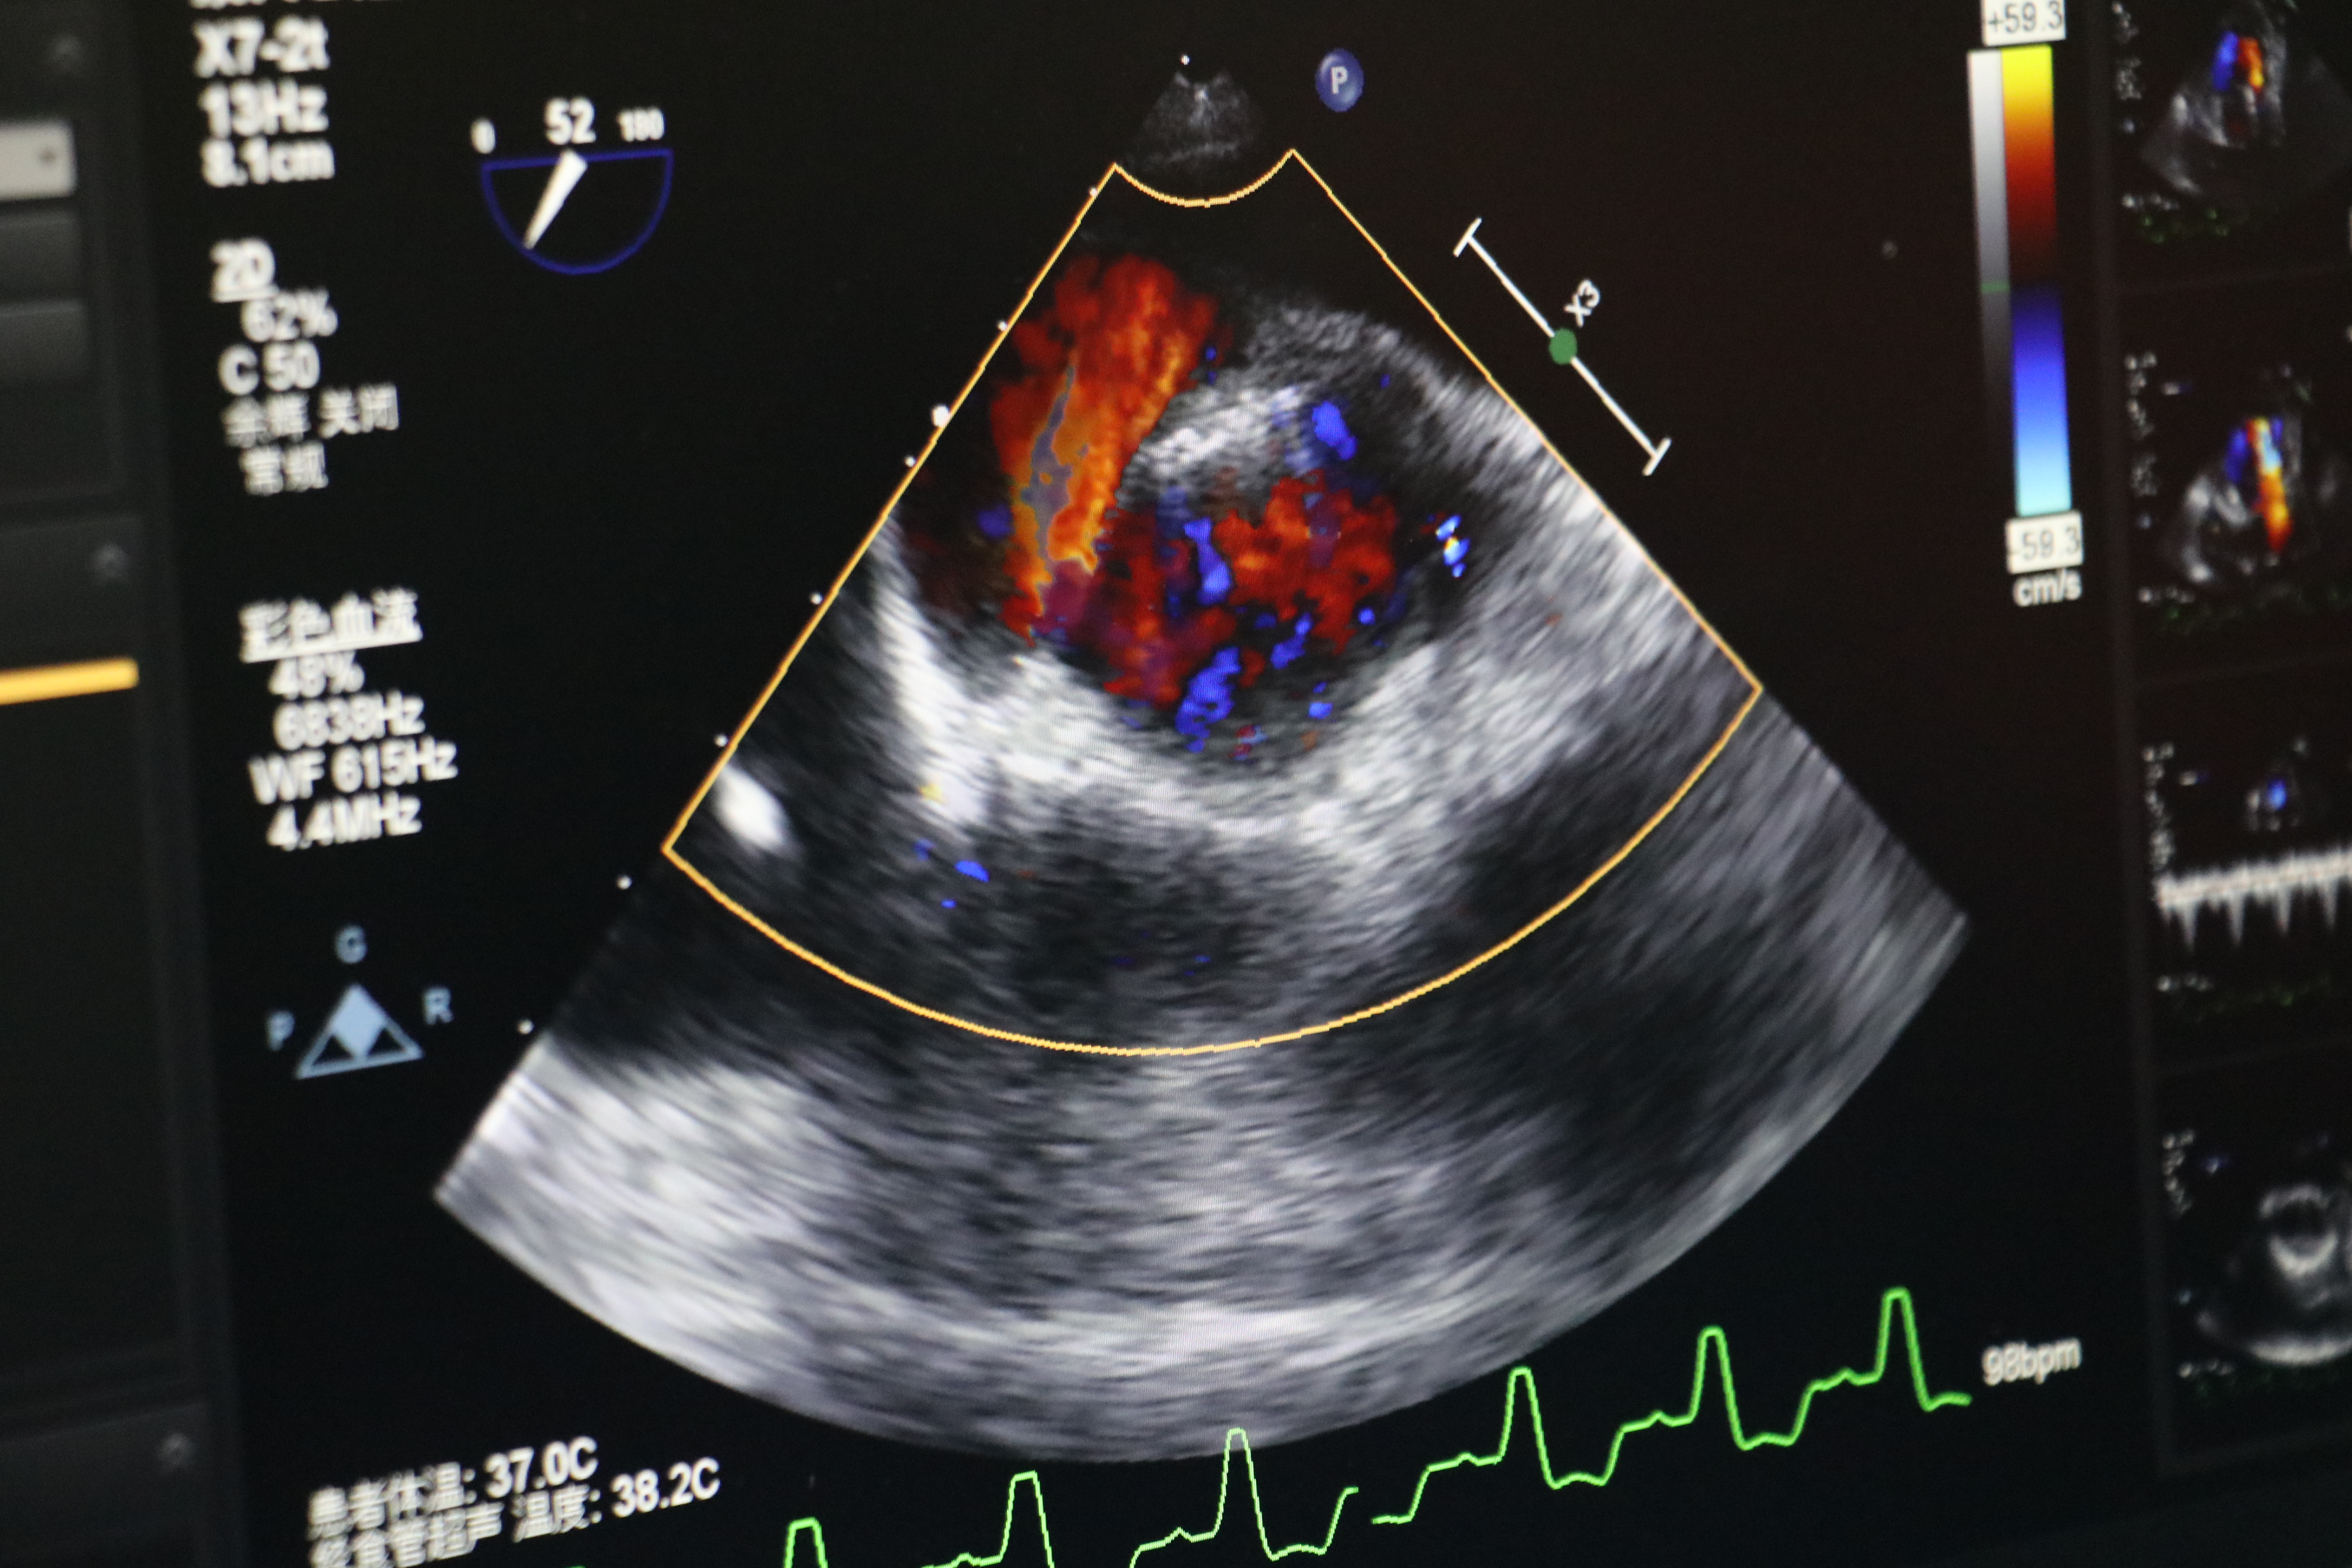

食道超声所示术中人工心脏瓣膜

再次造影及TEE发现:主动脉瓣无返流,介入瓣膜形态满意,无瓣周漏,无跨瓣压差。